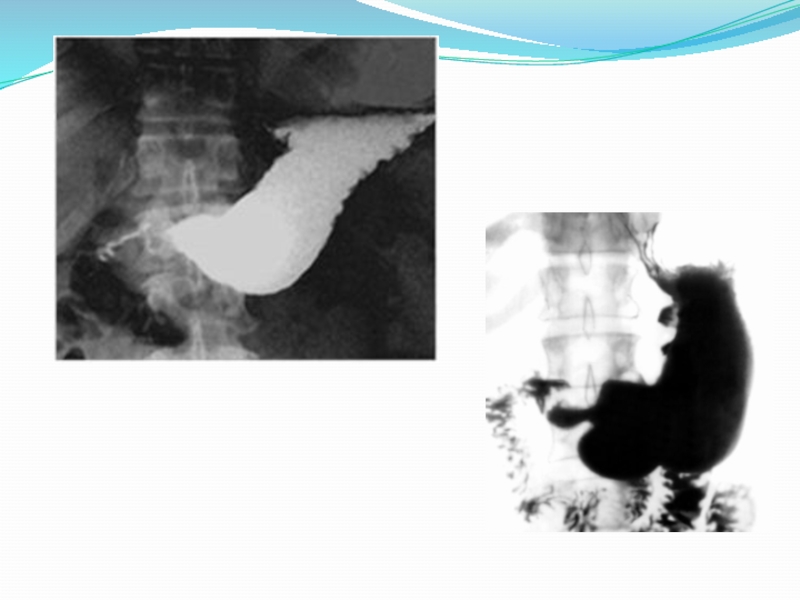

Слайд 6Диагностика

РЕНТГЕНОЛОГИЧЕСКОЕ ИСЛЕДОВАНИЕ

I стадия: несколько расширенный желудок, усиление его перистальтики, сужение

пилородуоденальной зоны. Полная эвакуация контрастной массы из желудка замедлена на

срок до 6—12 ч.

II стадия: желудок расширен, натощак содержит жидкость, перистальтика его ослаблена. Пилородуоденальная зона сужена. Через 6—12 ч в желудке выявляют остатки контрастного вещества.

III стадия: желудок резко растянут, натощак в нем большое количество содержимого. Перистальтика резко ослаблена. Эвакуация контрастной массы из желудка задержана более чем на 24 ч.